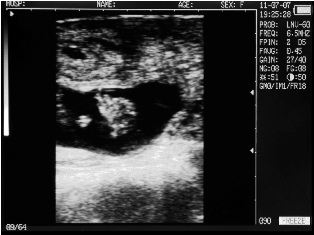

Cow with calf. Deadline - 30 days